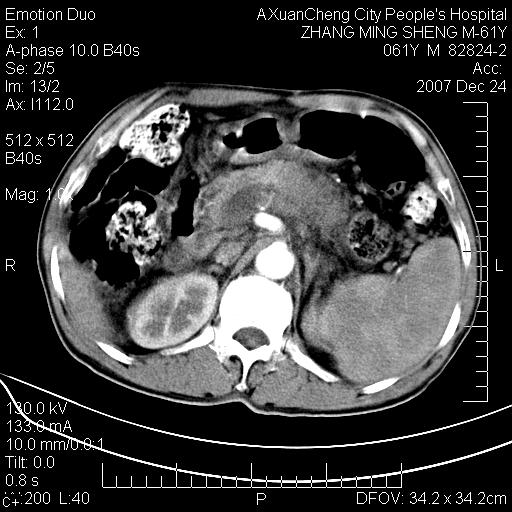

标题: CT11031:M61Y,胰腺占位

大家侃侃门静脉和胆管系统怎么回事,肝内转移?

胰腺癌肝转移

肝硬化,门脉高压,脾肿大;弥漫性肝癌,肝内、门脉、腹膜后淋巴结转移,肝内外胆管扩张,胰头区占位,建议mr检查

胰腺癌伴肝内转移;门脉、肠系膜上v癌栓形成。

考虑为:胰腺癌伴肝脏转移、腹膜后淋巴结转移,门静脉及肠系膜上静脉瘤栓形成。

胰体尾癌伴肝内转移,门静脉及肠系膜上静脉瘤栓形成.